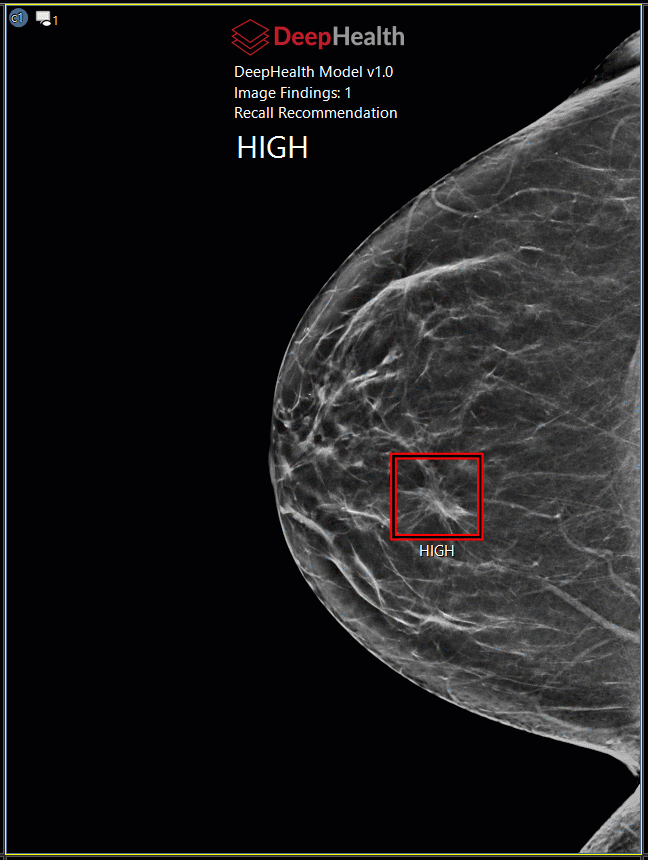

Mammography CAD Markers

A CAD marker provides computer-aided diagnosis to mammography images.

CAD Systems

The PACS has validated CAD Structured Report objects from the following CAD systems.

CAD Overlays

If a study includes a CAD marker, the presentation state icon (highlighted) appears in the top left corner of the image when it is displayed in an image frame.

CAD Certainty Scores

Some CAD vendors provide case scores for each study and or finding.  Case score can be found in the CAD header and an individual finding score can be found adjacent to the marking on the image.